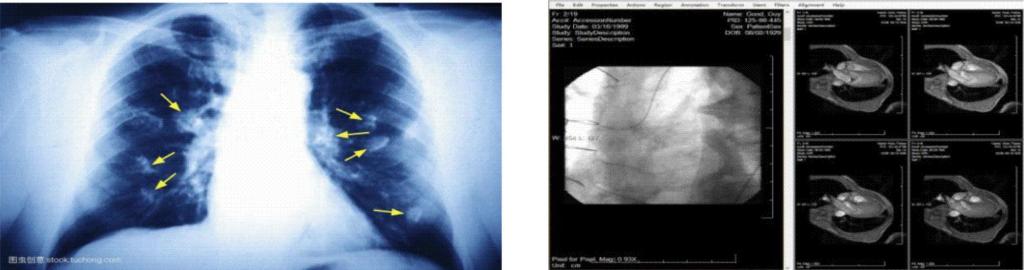

聚焦医疗影像处理技术研究与应用,针对医疗图像及影像,进行医学图像处理与分析。包含医学图像预处理技术,图像增强、降噪技术、人工智能和数值算法病灶自动检测及标注等。代表性研究成果如下:

病灶自动检测、标记技术